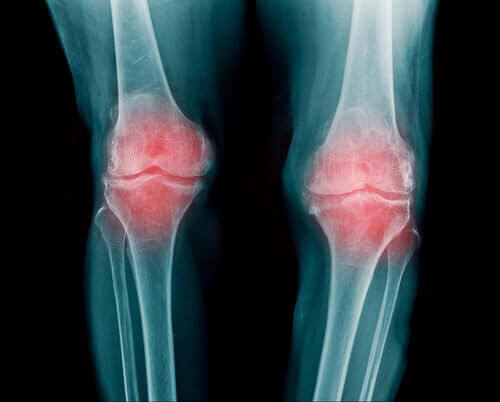

Je gewrichten bevinden zich aan de uiteinden van de botten in je lichaam. Daardoor vervullen ze een fundamentele rol in de beweging van al je ledematen. Overbelasting van de gewrichten kan verschillende ziekten veroorzaken. En één van deze aandoeningen is artrose.

Tussen elk gewricht bevindt zich een stuk kraakbeen. Dit voorkomt dat je botten over elkaar heen wrijven. Het verstrijken van de tijd veroorzaakt echter een geleidelijke afname van kraakbeen. Daardoor kan je last krijgen van ontstekingen en pijn.

Vervolgens wordt je beweging aanzienlijk beperkt. Hiermee neemt je vrijheid om andere activiteiten te doen af.

Volgens deskundigen ontstaat de pijn bij artrose door een ontsteking en niet door weefselslijtage. Aangenomen wordt dat de voornaamste reactie op weefselslijtage het ontstaan van zwellingen is.

Ondanks aanwezigheid van een ontsteking is artrose niet altijd pijnlijk (behalve in sommige gevallen waar het ongemak uit het niets opduikt). Een bepalende factor is de individuele pijngrens. Ieder lichaam is anders. En dat geldt ook voor pijntolerantie.

Met andere woorden: de pijngrens is afhankelijk van de gevoeligheid van de patiënt.